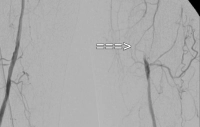

Ejemplo de vídeo: TASC C → reconstrucción abierta

EAP estadio IIb izquierda (distancia de marcha inferior a 100 m). La DSA preoperatoria muestra:

- una estenosis subtotal de la arteria femoral común

- una oclusión de largo recorrido de la arteria femoral superficial en el canal aductor

- oclusiones parciales de las arterias de la pierna inferior